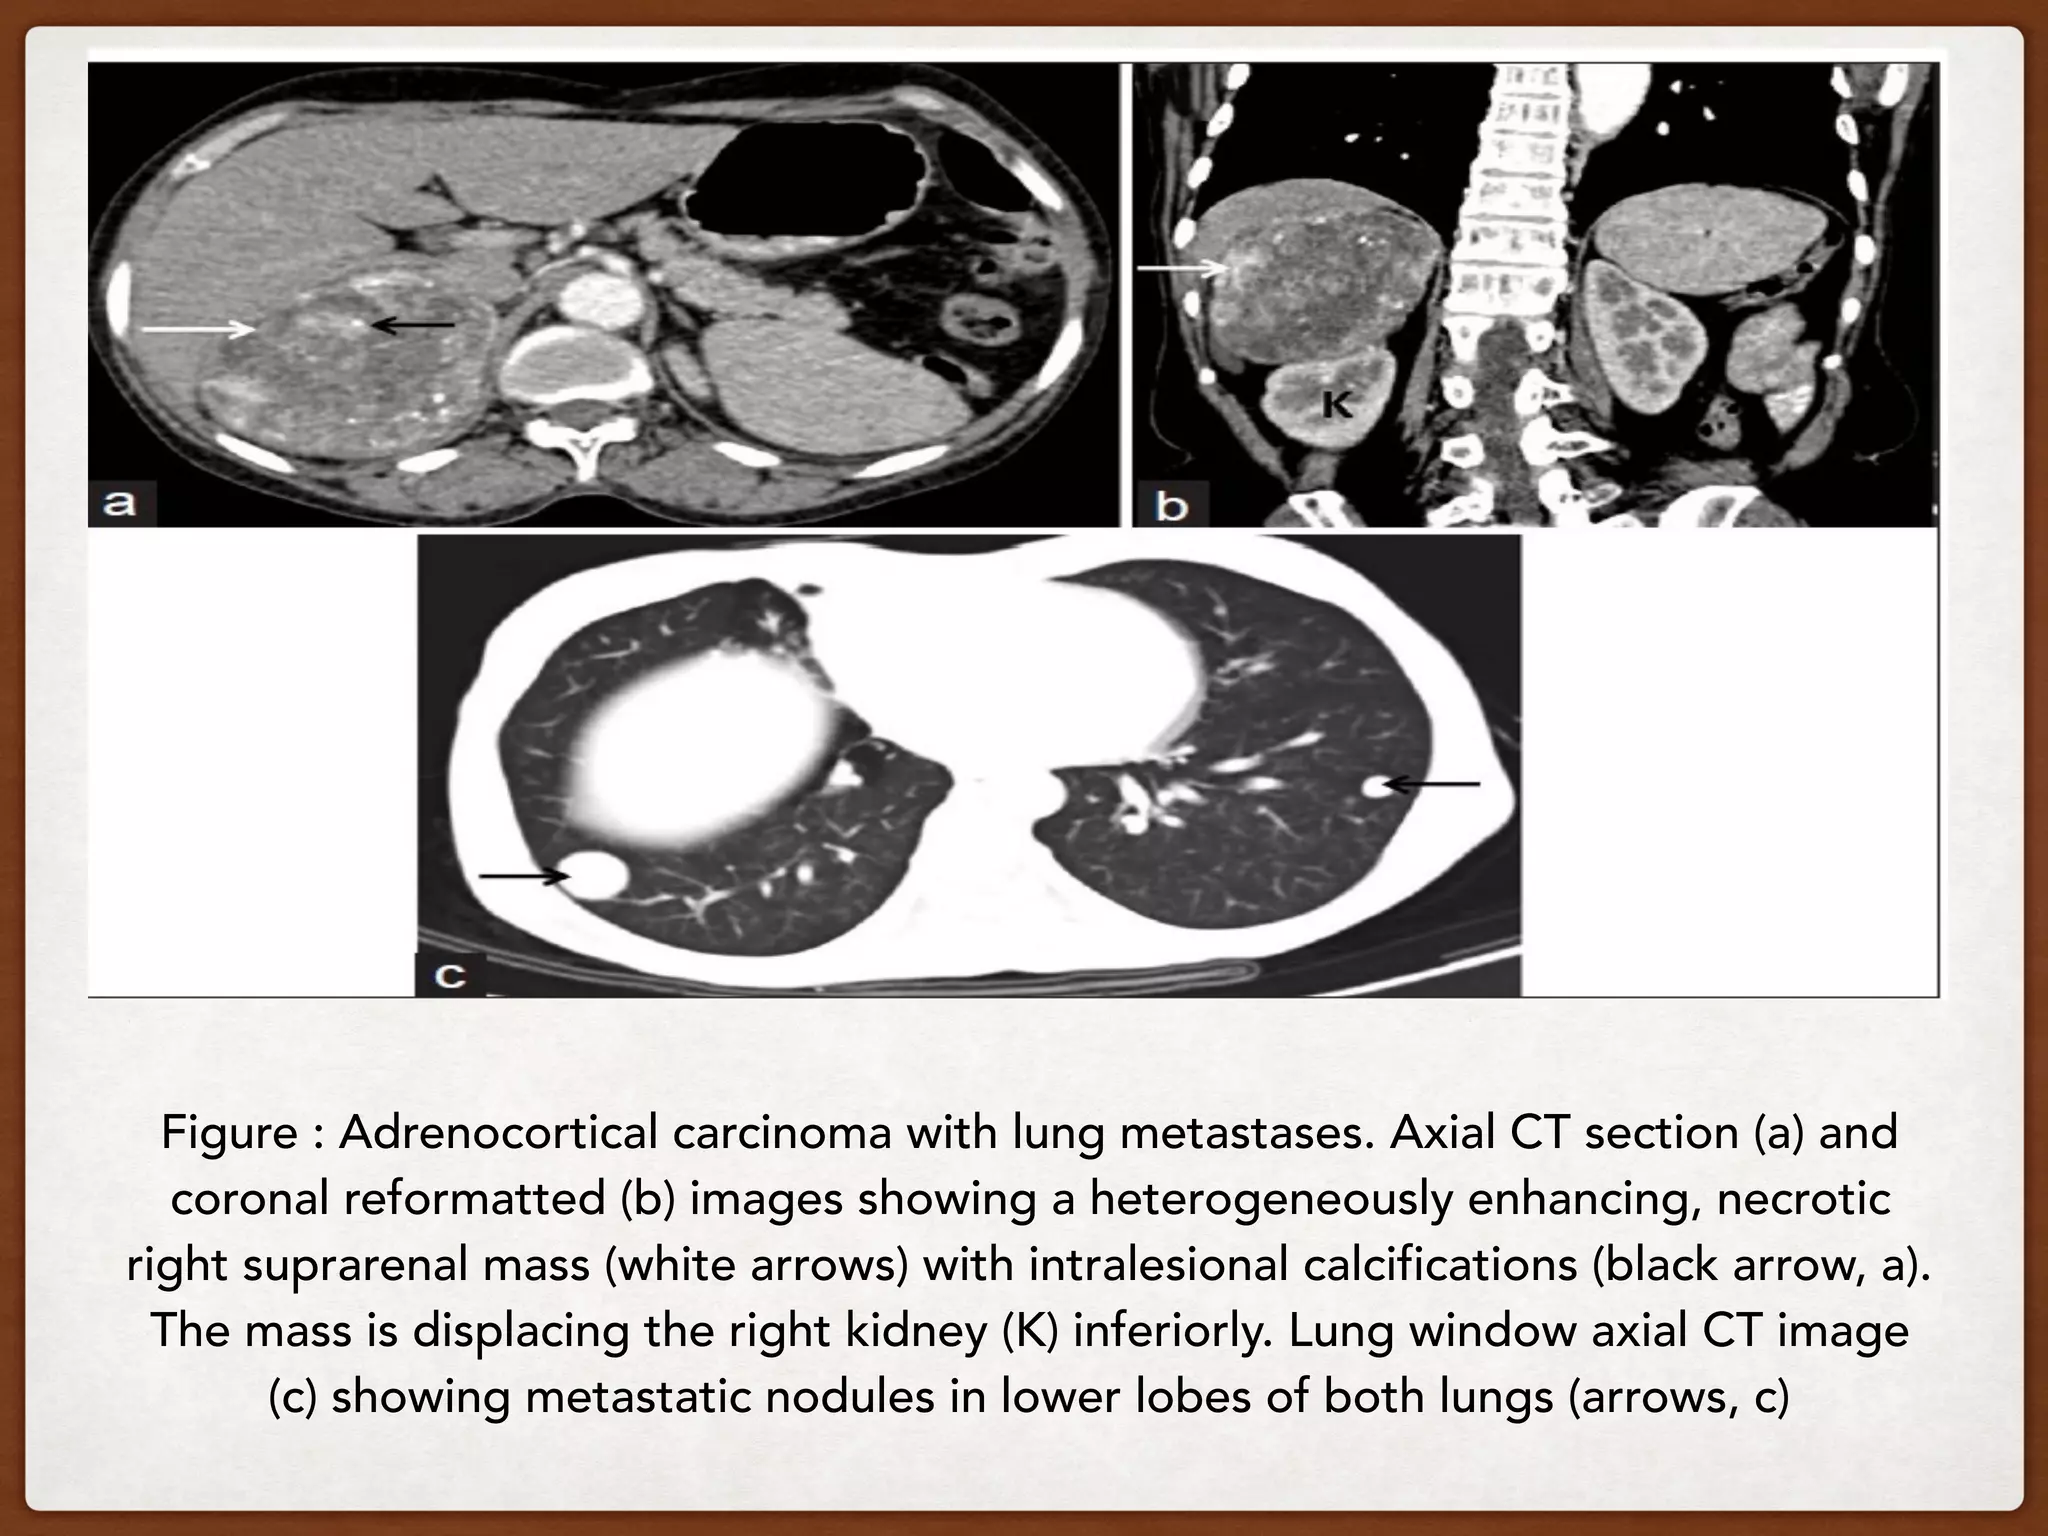

Figure : Adrenocortical carcinoma with lung metastases. Axial CT section (a) and

coronal reformatted (b) images showing a heterogeneously enhancing, necrotic

right suprarenal mass (white arrows) with intralesional calcifications (black arrow, a).

The mass is displacing the right kidney (K) inferiorly. Lung window axial CT image

(c) showing metastatic nodules in lower lobes of both lungs (arrows, c)